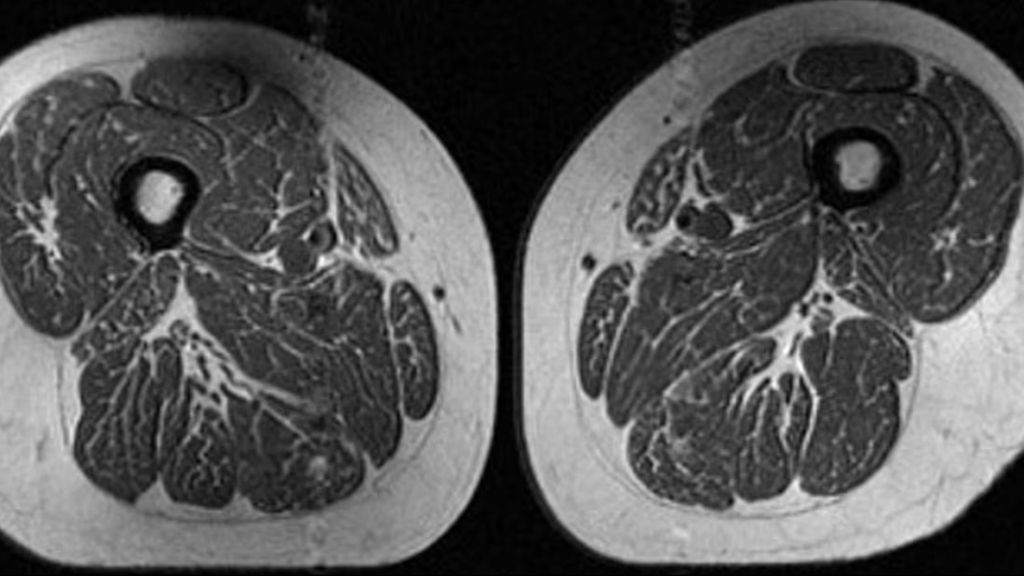

Suuri ultraprosessoidun ruoan osuus voi näkyä reisilihaksissa rasvana jo ennen polven nivelrikon merkkejä.